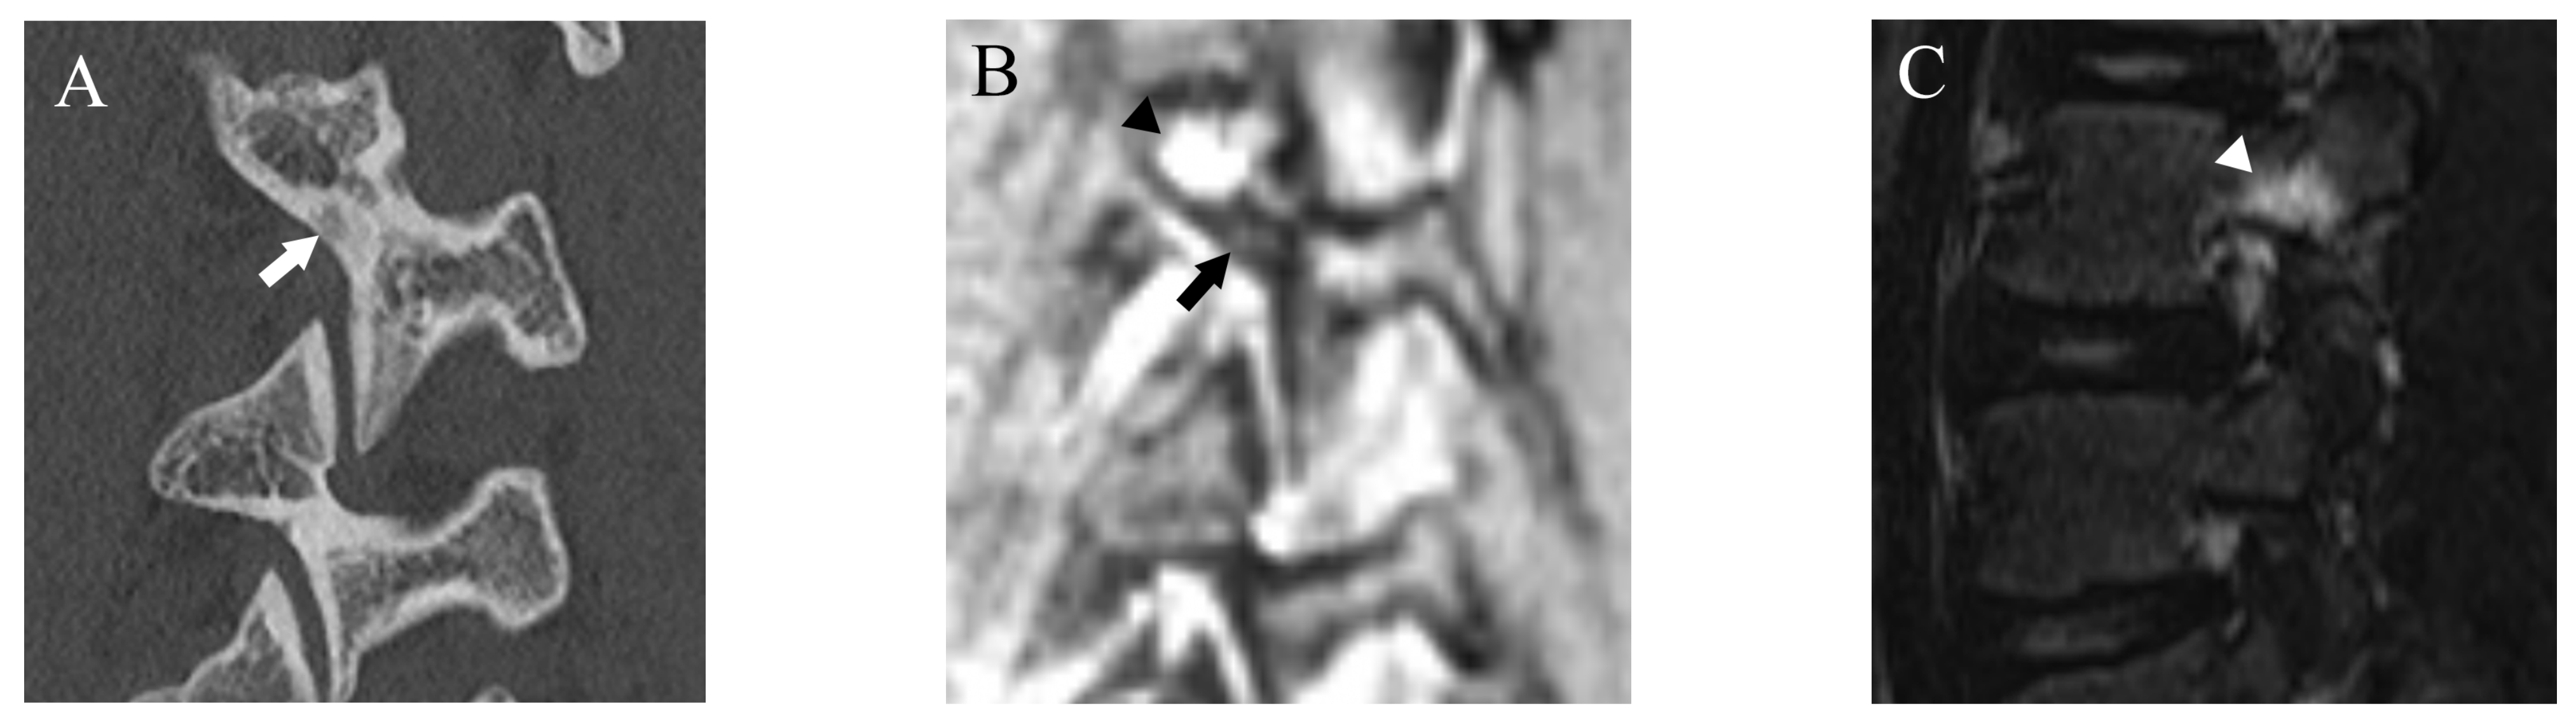

Figure 1.

Representative images of grade 1 fracture. The right pars interarticularis of L3 from a 14-year-old male. (A) Oblique-sagittal CT image showing faint attenuation in the cortex (arrow). (B) The faint attenuation corresponds to slight hyperintensity in the cortex on an oblique-sagittal DESS image (arrow). The window of the image was adjusted to enhance the faint finding. Note the BME in the pedicle (arrowhead). (C) Sagittal STIR image shows BME in the right pedicle of L3 (arrowhead).

After more than a 2-week interval from creating standard references, two readers independently analyzed fractures on T1WI and DESS using the same grading system as used in CT. On MRI, bone resorption (grade 1) can be detected as slight hyperintensity within cortical bone which normally shows homogeneous hypointensity (Figure 1). The fracture line on MRI is delineated as linear hypointensity on T1WI and linear hyperintensity on DESS (Figure 2 and Figure 3). DESS was also used to evaluate the BME binary. Similar to STIR, if there is a high signal at pars interarticularis on DESS, it is considered positive for BME. Consensus results for T1WI, DESS for fracture and DESS for BME were created for statistical analysis.